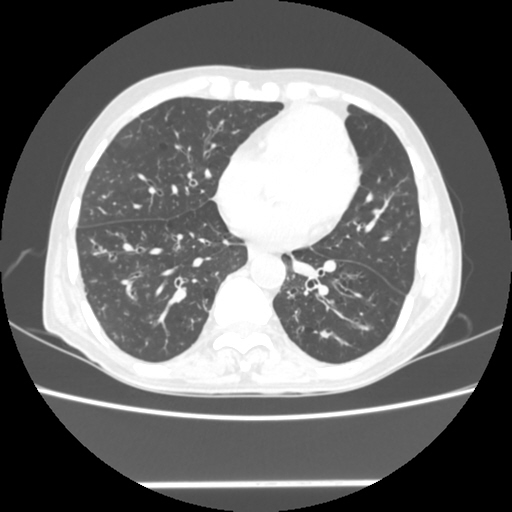

A 54 years old man with intermittent cough with expectoration and shortness of breath since childhood (Radiology)

Radiological images: